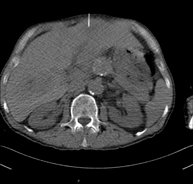

Biopsia abdominal guiada por TCConsiste en obtener una muestra de tejido de una determinada lesión localizada en la cavidad abdominal. A veces se realiza bajo sedación, con la ayuda del equipo de anestesia. Se utilizan agujas que permiten la obtención de un cilindro de la lesión a estudiar que se enviará a Anatomía Patológica para su análisis histológico. Todo el procedimiento se realiza controlado con imágenes obtenidas por Tomografía Computarizada (TC) en varios momentos de la biopsia, mediante el empleo de Fluoroscopia-TC. Tras la prueba, el paciente permanece hospitalizado para controlar su evolución. Es necesario aportar pruebas de coagulación antes de la punción.